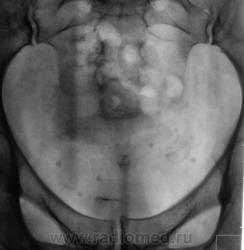

После введения контрастного вещества урограммы произведены на 7 и 15 минутах.

Да, контраст "покрыл" тень рентгеноположительного конкремента.

А мне этот конкремент, при всей его "рентгеноположительности", видится дефектом наполнения чашки, контрастированной ещё более "рентгеноположительным" контрастом)).

Ещё более отчетливо это может было бы увидеть на прицельной рентгенограмме почки либо томограмме её.